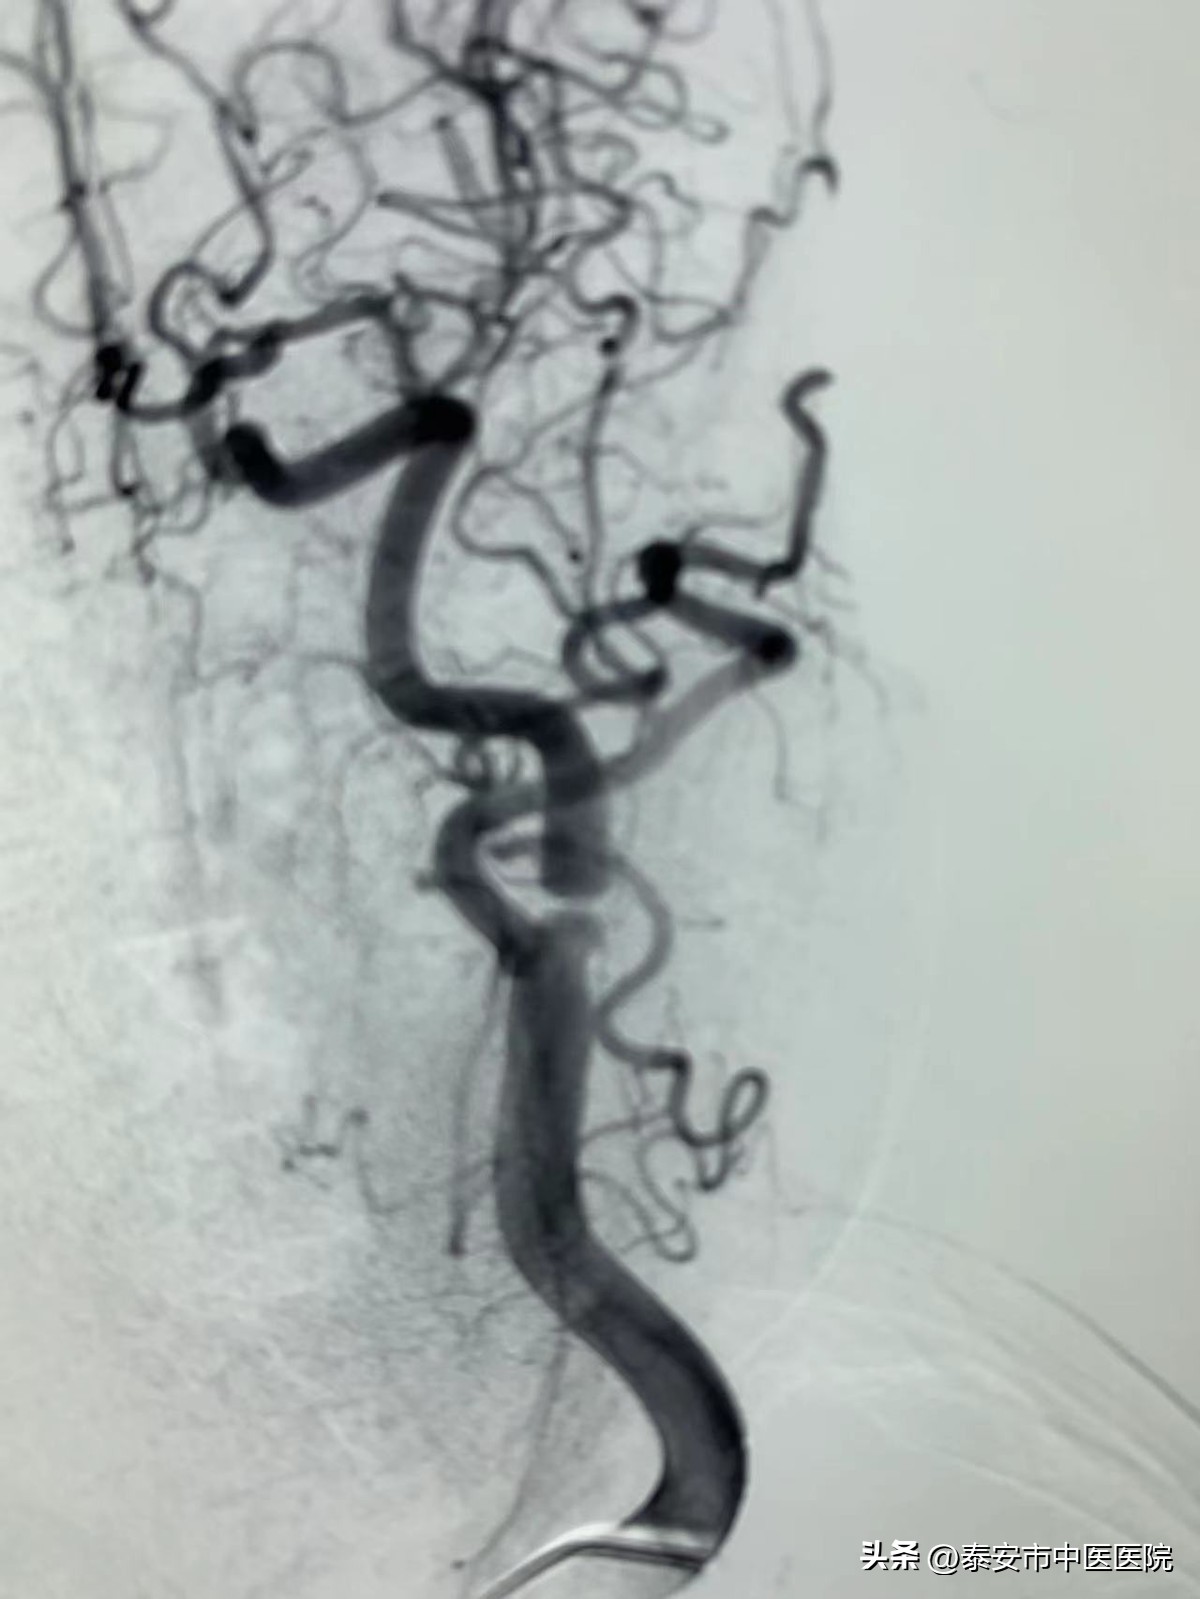

据悉,69岁的李大娘(化名)因头晕、恶心、行走不稳等症状到*安泰**市中医医院就诊。入院后在进行脑血管造影时,脑病外科主治医师牛常存发现:患者多发脑动脉狭窄,其中左侧颈内动脉起始段重度狭窄,狭窄程度达到90%,如不及时进行手术,脑卒中的发生率极高,严重时可能危及生命。与家属积极沟通病情后,牛常存同时向主任医师王其瑞进行了汇报。

在询问病史并详细查看检查结果后,王其瑞发现患者不但有冠心病,还合并糖尿病、高血压等基础疾病,手术风险高。在充分评估患者身体状况及手术风险后决定行颈动脉内膜剥脱术。经专家会诊后,科室制定出详细的手术方案,力求万无一失。